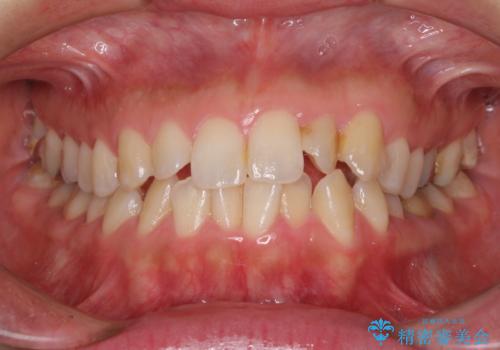

- 前歯の捻れを気にして来院された患者様です。

上顎前歯が捻れて前方に飛び出しており、下顎前歯もそれに沿うようにデコボコとなっていました。

IPR(歯と歯の間を削る処置)によりスペースを獲得して上下前歯のデコボコを改善し、インビザラインにて矯正治療を行うこととしました。